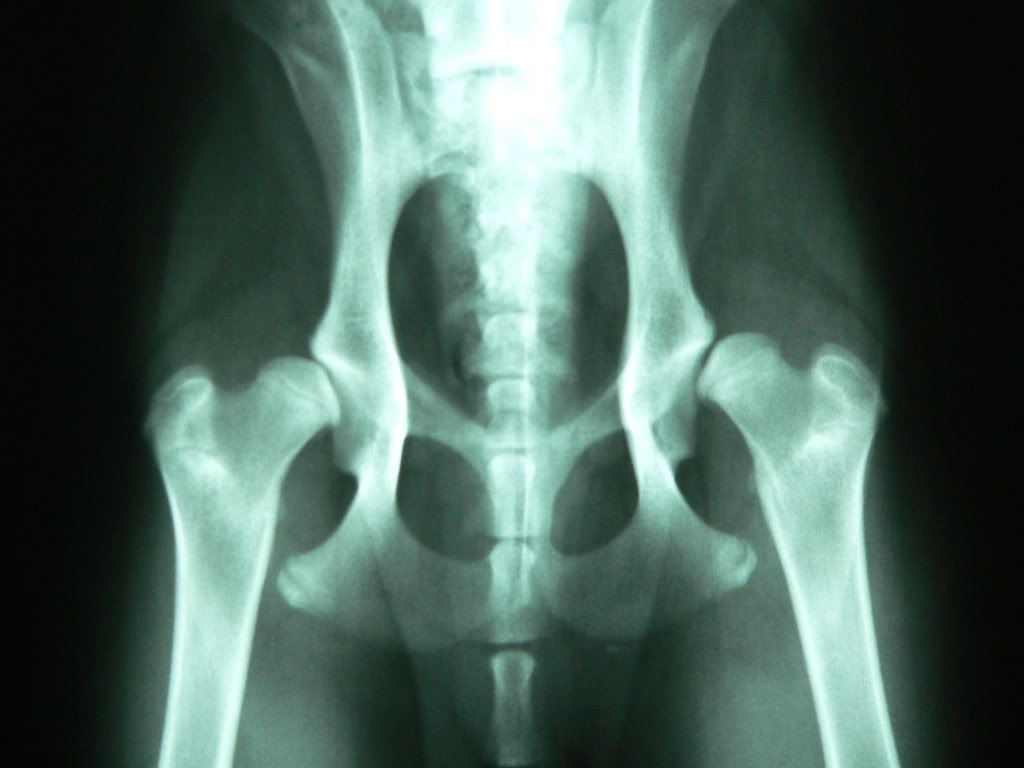

ДТБС у собак: рентгенограммы

Кликните на картинку для её масштабирования

Галерея изображений доступна только в электронном виде по следующему адресу::